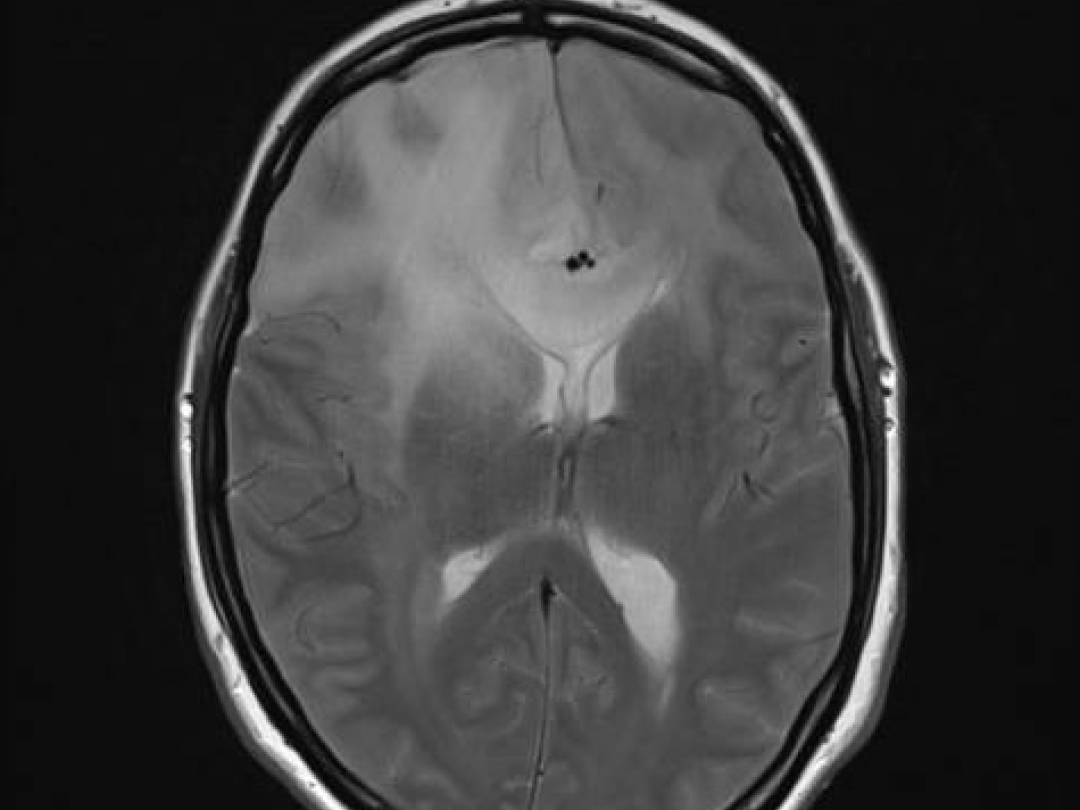

Een 38-jarige zwangere vrouw werd bij een amenorroeduur van 31/5 weken op de Spoedeisende Hulp gezien vanwege een gegeneraliseerd tonisch-clonisch insult. De waarschijnlijkheidsdiagnose was een eclamptisch insult vanwege hypertensie bij opname. Ondanks behandeling met magnesiumsulfaat had zij recidiverende insulten. Daarom werd beeldvormend onderzoek verricht. Er bleek sprake van een hooggradig glioom. De patiënte is bij 37 weken zwangerschap bevallen van een gezonde dochter en werd daarna palliatief behandeld met chemotherapie.